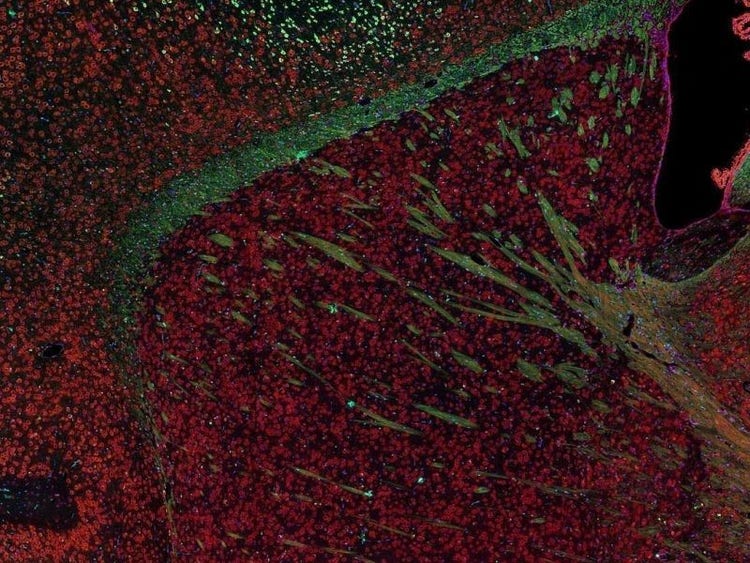

Fluorescence imaging of a mouse brain

尽管每幅图像近看各不相同,但将其拼接在一起则可组成一幅小鼠大脑的荧光图像。

英国科学家乔治·斯托克斯在用紫外线照射矿物萤石时首次观察到了矿物萤石发出的荧光,并创造了“荧光(fluorescence)”这个词。斯托克斯注意到荧光的波长比激发光的波长更长,这种现象现在被称为斯托克斯位移。无论是自然具有荧光的材料(称为原发荧光或自发荧光),亦或是经过有机染料处理后产生荧光的材料(称为次生荧光),荧光显微镜都是研究这些荧光发光材料的最佳工具。